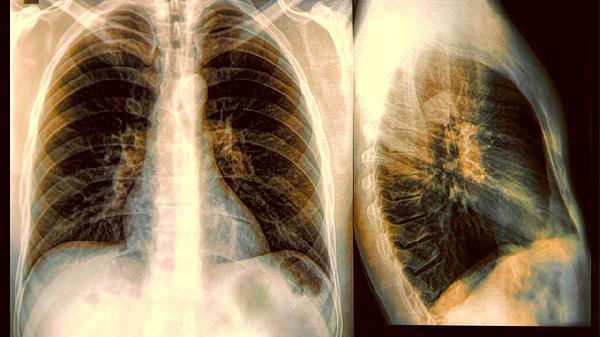

典型哮喘通过肺功能检查显示可变气流受限确诊;变异性哮喘需结合支气管激发试验或呼气一氧化氮检测,肺功能往往正常。约60%的变异性哮喘患者存在气道高反应性,但程度较典型哮喘轻。